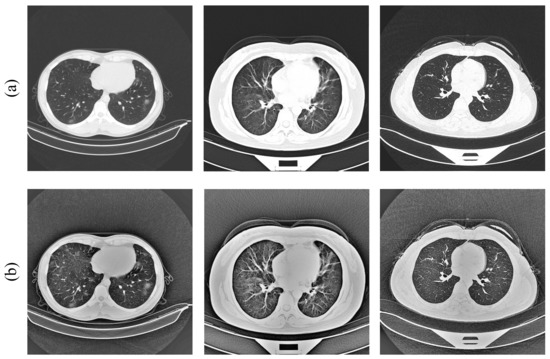

However, because of the disadvantage that MSR often suffers from “halo” artifacts and low contrast, we first converted the CT images from RGB to grayscale to reduce the amount of computation, and then used the CLAHE [46] method to enhance the contrast of the image, as well as to avoid the loss of image details. Compared to the traditional adaptive histogram equalization (AHE) method, CLAHE is more able to overcome the problems of AHE, such as amplified noise regions in the image, and can better extract the lesion areas. The results of the image preprocessing are shown in Figure 3.

Figure 3.

(a) Original images; (b) processed images [11,12].